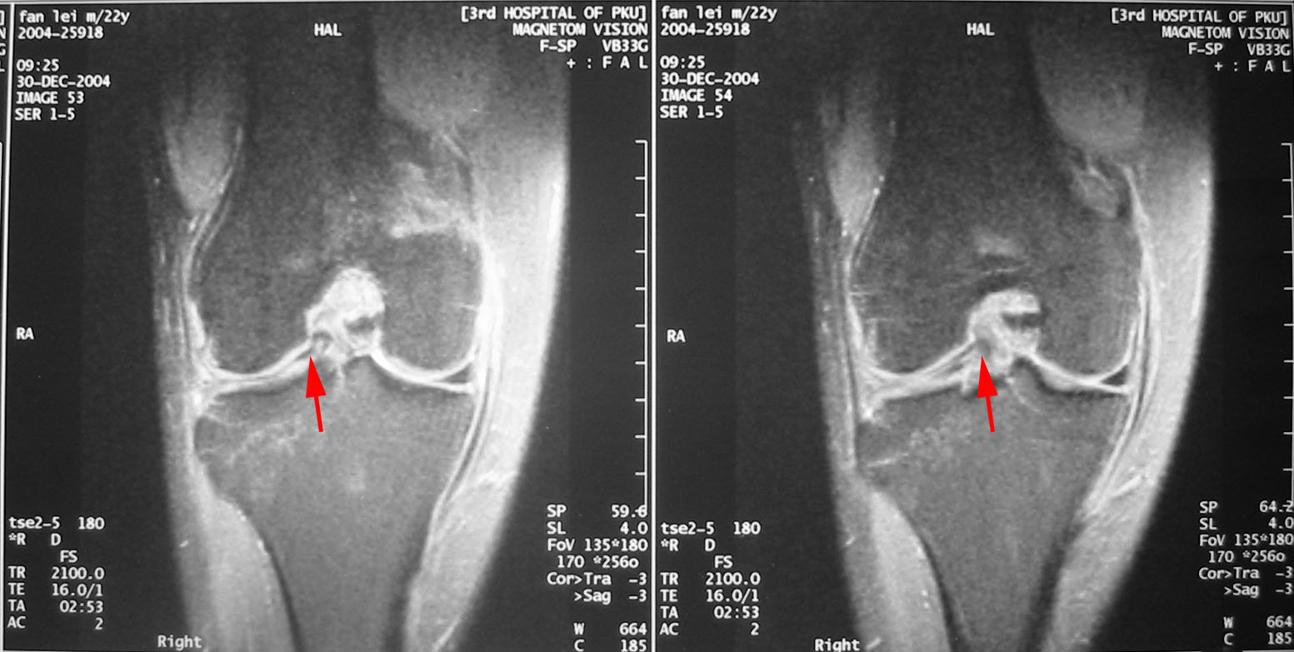

(1)半月板损伤了,一般需要进行膝关节磁共振检查(MR),可以明确半月板损伤的程度。MR下半月板损伤分为三度:

0度MRI表现正常,均一信号;

Ⅰ度和Ⅱ度MRI表现为半月板内部高信号,但不到达半月板表面;

Ⅲ度MRI表现为半月板内略高信号线累及半月板的关节缘,提示半月板撕裂。

(2)一般情况下,I-II度的MR表现是不需要手术治疗的,多数中老年人半月板MR表现为I-II度损伤,属于正常退变现象,一般无需治疗。而部分Ⅲ度损伤需要手术治疗。